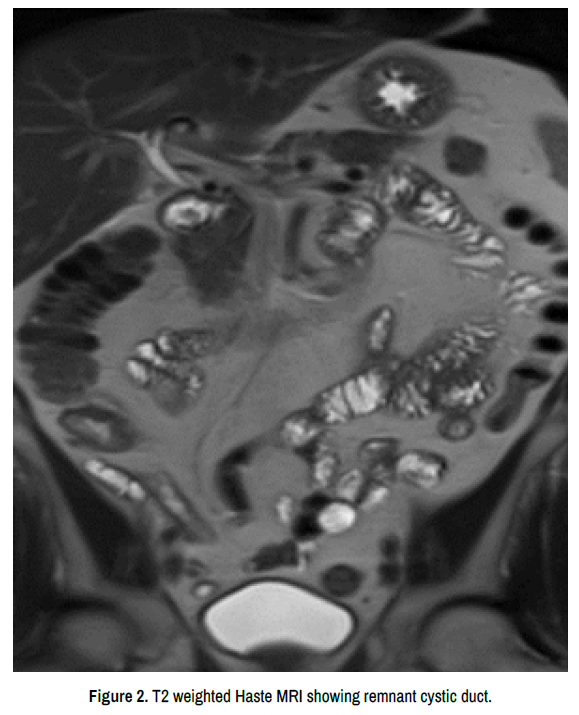

MRCP revealed no evidence of intra- or extrahepatic cholestasis and showed clipping artifacts in the area of the elongated ductus cysticus remnant of 3 cm. A calculus within the remnant ductus cysticus was suspected but could not be definitively confirmed. Mild chronic inflammation was present around the remnant duct. The pancreaticobiliary junction was normal. Additional targeted ultrasound confirmed a stone in the remnant cystic duct (Figures 1 and 2).

Figure 2. T2 weighted Haste MRI showing remnant cystic duct.